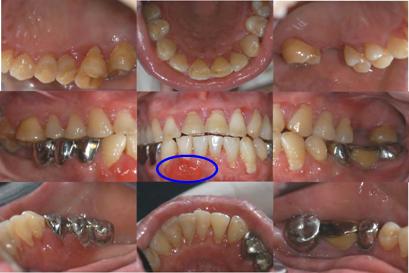

治疗后评价:

本例为前牙区药物性牙龈增生伴后牙区重度牙周炎,经过牙周基础治疗和两次间隔期在2-4个月的维护治疗后,前牙15×10mm的牙龈增生肿胀消失痊愈;全口4-8mm的牙周袋均减少至3-4mm以内;后牙区多个位点的角形骨吸收得到显著再生恢复;结合患者有效的自我菌斑控制,远期疗效佳。

治疗后一年口内相